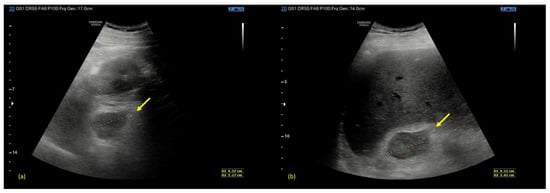

Therefore, he was immediately subjected to a computed tomography (CT) scan of the abdomen before and after the administration of contrast medium (Omnipaque 350 mgI/mL, 130 mL, 3 mL/s), with a 1.25 mm slice width, 120 kV, and 7 mAs. The non-contrast phase demonstrated slightly hyperdense round masses with fuzzy margins and a diffuse swelling of both adrenal glands, associated with inflammatory changes in the surrounding retroperitoneal fat, confirming the presence of a bilateral adrenal hemorrhage (Figure 2a). After the intravenous contrast, no enhancement was revealed (with density values of 45–55 HU both in pre-contrast and post-contrast phases) and no ”blushes” were revealed, suggesting no evidence of active bleeding (Figure 2b–d).

Figure 2. (a) CT axial non-contrast phase. (b) CT axial post-contrast arterial phase. (c) CT axial post-contrast portal venous phase. (d) CT coronal non-contrast phase. Arrows indicate the adrenal glands. The non-contrast phase demonstrates slightly hyperdense round masses with fuzzy margins and diffuse swelling in both adrenal glands, in association with inflammatory changes in the surrounding retroperitoneal fat, which is strongly suggestive of bilateral adrenal hemorrhage. After the intravenous contrast, no contrast blushes are shown, suggesting no evidence of active bleeding.

Computed Tomography (CT) is the most important tool in the diagnosis of adrenal bleeding. Adrenal hematomas can typically be detected in the non-contrast phase, where they appear as round to ovoid lesions, usually associated with periadrenal fat stranding and, sometimes, the involvement of the peri-nephric space. The acquisition of post-contrast phases (arterial, venous, and excretory) is crucial to detect any presence of active bleeding, seen as an arterial “blush” [15].

As for the CT density values of an adrenal hematoma, they depend on its stage. In the acute stage, a hematoma usually contains high attenuation areas (between 50 and 90 HU); as time goes on, its size and attenuation values decrease and, in some cases, a complete resolution can be seen.

The typical appearance of a chronic hematoma is a hypodense mass with internal calcifications [16]. An “adrenal congestion”, which consists in the thickening of the adrenal glands and stranding of the periadrenal fat, can be occasionally detected before the hemorrhage [17].